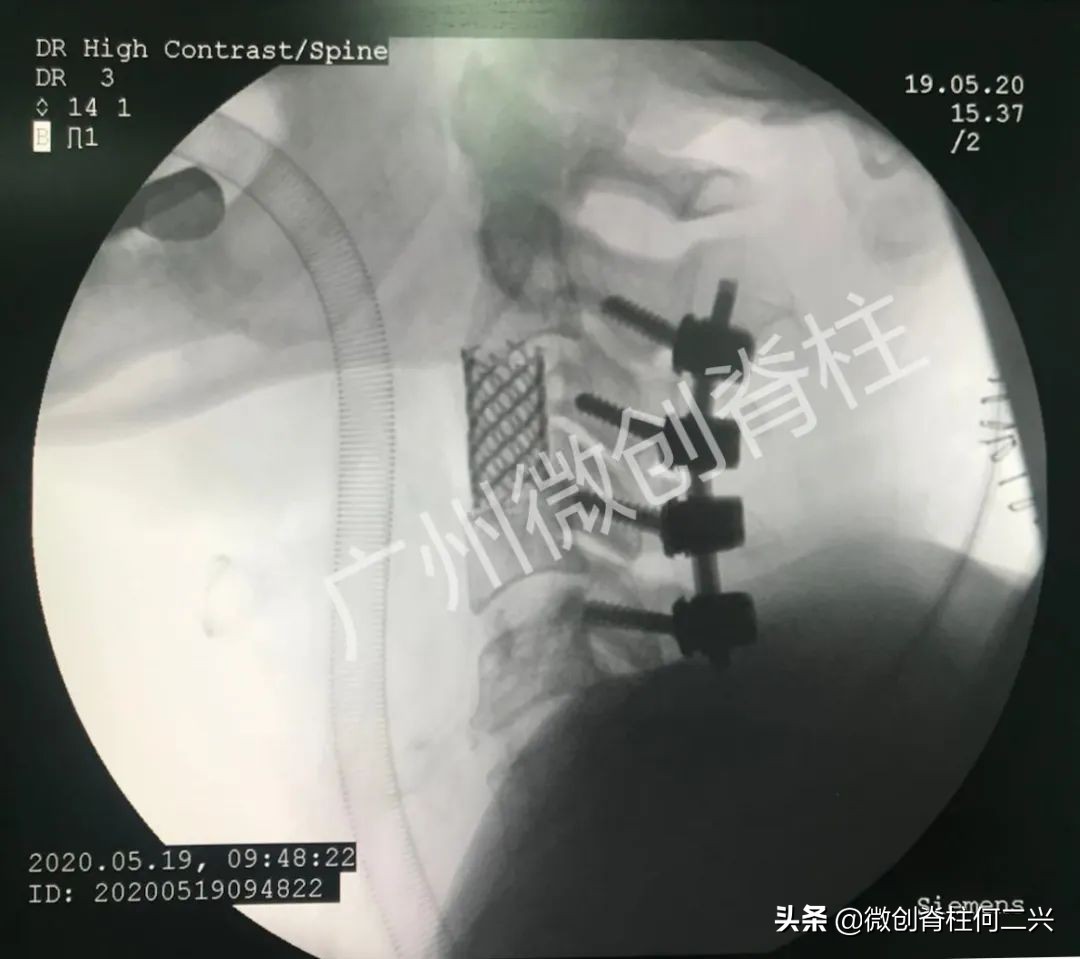

根据上述考虑,做出手术以下规划

从颈的后方先固定颈椎,防止术中造成脊髓伤害;第二步从颈的前方暴露第三椎体,用最先进的微波消融针精细布局插入椎体,将整个椎体的肿瘤细胞全部杀死,被微波消融的组织已经没有血液循环,手术医生轻松切除肿瘤组织;最后在已经掏空的原来第三颈椎的位置,装上钛合金做的固定装置,支撑颈椎,使其获得满意的稳定性。

由于术前的精准规划和术中的精准实施,切除肿瘤出血不够200毫升,手术后第一天患者即可起床活动,脊髓神经功能完整。再次体现精准微创手术的高超技巧。